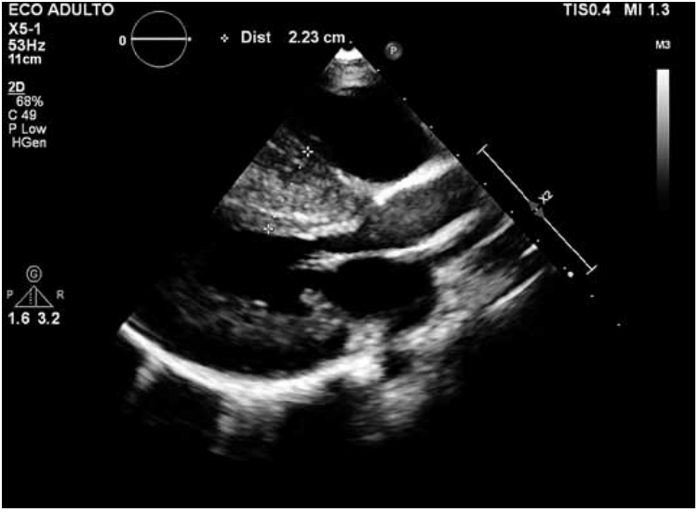

Paciente de 4 anos, masculino, deu entrada no pronto-socorro com cansaço progressivo. Realizou radiografia de tórax, eletrocardiograma e ecocardiograma (figura a seguir).

Enunciado 3561506-1

O diagnóstico que se pode dar a esse paciente é